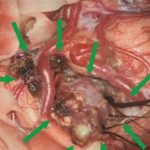

'19年5月

30代

富永/久貝

右中小脳脚 出血再発

SM 3(S1,E1,V1)

米国の病院

No.359 モニタリング

No.359 手術前

No.359 手術中

No.359 手術後

出血既往があり。2回の手術前血管内手術の後に、

Lateral transpeduncular approachにより再々出血予防を目的に

摘出手術を行う。完全摘出であることを確認した。

手術による合併症や後遺症なしで退院した。経過良好。